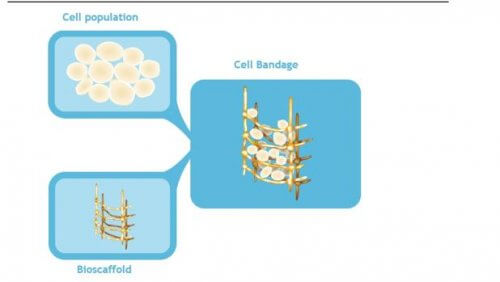

그 방법은 바로 환자의 줄기세포로 만드는 “살아있는 붕대(living bandage)”다. 이것은 환부의 세포 성장을 촉진하고 파열되거나 손상된 조직을 복구한다.

Stem Cells Translational Medicine 저널은 이 연구를 발표했다. 여기에서는 “세포 붕대”가 어떻게 파열된 반월상연골의 치유를 촉진하는지에 대해서 논한다.

- 먼저 연구자들은 환자의 골수에서 줄기세포를 추출했다.

- 이들은 2주간 실험실에서 이 세포들을 배양했다.

- 그 후 이들은 세포막 구조에 성숙 세포를 사용했다.

- 이것은 파열된 반월상연골에 이식되었다.

- 연골이 봉합되어 이것을 덮은 다음 안정화한다.